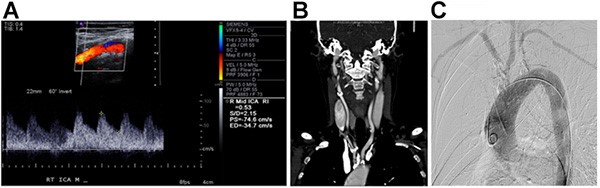

A woman in her midfifties presented to the vascular surgery clinic with several months of bilateral upper extremity numbness and weakness with activity. She also experienced frequent drop attacks consistent with vertebrobasilar insufficiency and had a heavy smoking history. She had no neck pain, no neck stiffness, and no laboratory signs of systemic inflammation. Her medical history was significant for coronary artery disease requiring two prior coronary stents, atrial fibrillation, and hypertension. Physical examination revealed cool hands, bilateral upper extremity hypotension, and the absence of upper extremity arterial pulses without evidence of ischemic tissue loss or neurological deficits. There were no abnormalities on laboratory examination. Carotid duplex ultrasound revealed no visible plaque and no evidence of intimal flap or dissection. At this point, the differential diagnosis included thromboangiitis obliterans, atherosclerosis of the supra-aortic trunks, giant cell arteritis, and cervical degenerative disk disease. Computed tomography angiogram revealed high grade stenosis of the brachiocephalic artery, bilateral proximal common carotid arteries, and proximal and distal left subclavian artery; a large dominant left vertebral artery; and an occluded right vertebral artery. Subsequent catheter-based angiography confirmed these findings and revealed significant coronary artery disease as well (Figure 1). At the time of catheter based angiography, central blood pressure measured in the thoracic aorta was 168/58.

Figure 1. This patient’s carotid artery duplex ultrasound (A) showing normal carotid artery waveforms and velocities, (B) computed tomography angiogram showing supra-aortic trunk vessel lesions, and (C) aortic arch angiography with heavy atherosclerotic burden in the supra-aortic trunk vessels.

Given the patient’s history as a middle-aged woman with a history of smoking with upper extremity exercise-induced fatigue, vertebrobasilar symptoms, and absent upper extremity arterial pulses, she was diagnosed with atherosclerosis of the coronary arteries and supra-aortic trunk vessels resulting in chronic upper extremity ischemia and cerebrovascular malperfusion resulting in vertebrobasilar insufficiency.